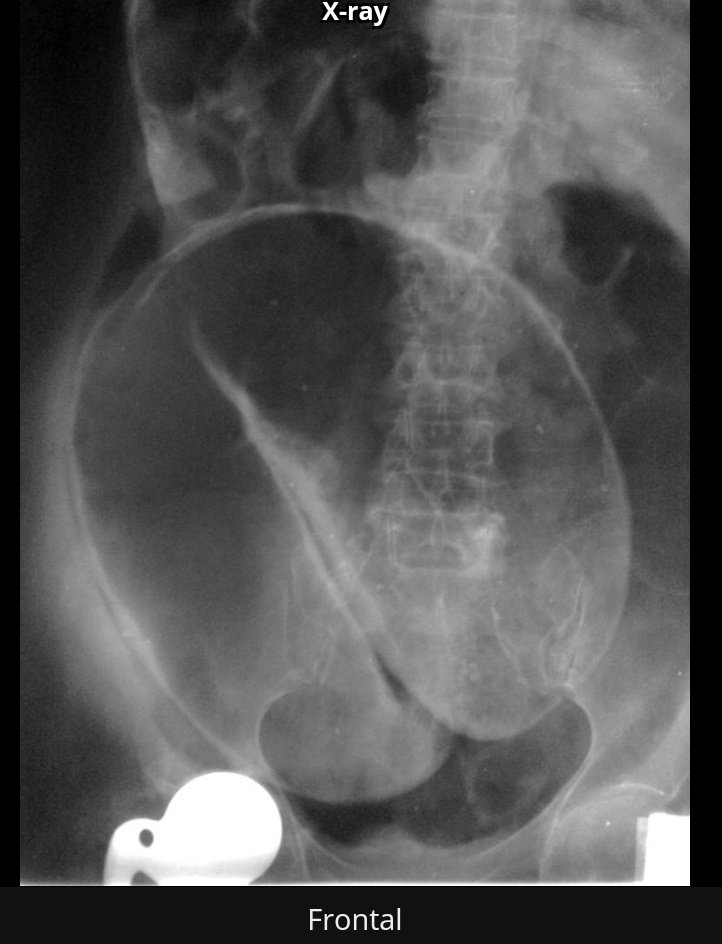

علامة ميكي ماوس

Mickey mouse

كدلالة على

bilateral Hutch diverticula

ويتضح انبعاج مزدوج للمثانة مع ارتجاع في الحالب الأيسر